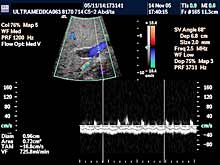

Posebni pregledi:

- Mogu biti nastavljeni nakon standardnog pregleda ako

zato postoje indikacije, ili

- postoje razlozi koji indikuju odmah

poseban pregled!

- Fokalne promene jetre, pankreasa i ostalih parenhimatoznih organa (3D

Sono CT procena i procena vaskularizacije sa Broad band-CD i PD i 3D

CPA modom).

- 3D Sono CT žučne kese i žučnih i pankreasnih puteva.

- Broadband-CD i CPA pregled portne cirkulacije

- Broadband-CD celijačnog pleksusa

- Broadband-CD procena leve renalne vene.

- Broadband-CD i CPA Aorte i ilijačnih arterija.

- Broadband-CD i 3D CPA bubrega

- Broadband-CD i CPD renalnih arterija

- 3D Sono CT i 3D CPA promena na tankom i debelom crevu

- 3D Sono CT želudca i intra abdominalnog dela jednjaka (hidrograstična

sonografija)

- 3D Sono CT debelog creva (HIDROKOLON).

- Sono CT, Xres, CD, CPA slepog creva.

- 3D Sono CT mokraćne bešike.

|